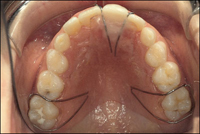

• Giữ khoảng tháo lắp: Được chỉ định trong trường hợp mất nhiều răng trên cùng một cung răng, hàm lưu giữ được nhờ sự thích ứng tinh tế với niêm mạc và các móc. Ưu điểm của loại này là: thăng bằng cơ học, phục hồi được thẩm mỹ và phát âm, lập lại được kích thước dọc của khớp cắn, không cần thiết mài răng trụ, cho phép thực hiện các chức năng nắn chỉnh, có thể sửa chữa thích ứng với sự thay đổi của cung răng, dễ vệ sinh và không ảnh hưởng đến vệ sinh cung răng. Bên cạnh đó, hàm tháo lắp này vẫn còn một số nhược điểm như: gây vướng trong miệng, tác dụng phụ thuộc nhiều vào sự hợp tác của bệnh nhân, giá đắt, dễ bị mất và gãy vỡ, có thể cản trở sự phát triển. Do vậy hàm này được chỉ định trong trường hợp: mất nhiều răng, mất 2 bên răng hàm sữa thứ 1 và 2, thiếu răng trụ và mắc giữ không đủ.